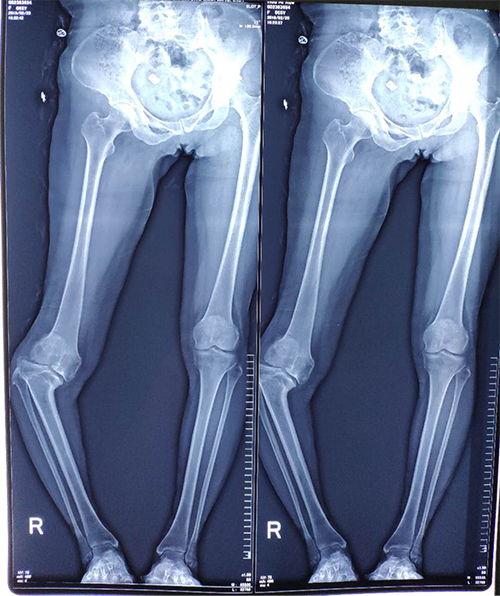

Blount病是一种特发性、非生理性的膝内翻畸形,特点是胫骨近段干骺端后内侧部分骨骺的局部生长紊乱导致的胫骨内翻成角畸形。该患者右膝关节疼痛伴内翻畸形40年,症状逐渐加重,行走跛行,严重影响日常生活,遂来我院骨关节科就诊,拟行手术治疗。

我院骨关节外科收治后,考虑该患者病史长,右膝内翻畸形约35°,合并创伤性关节炎,股骨远端及胫骨近段均存在畸形,手术难度大。经科室积极讨论,最终决定采用二期手术治疗方案,一期先行截骨矫形术+钢板内固定术,改善患者右下肢力线,康复后二期再行右侧人工膝关节表面置换术,本次住院期间先行一期手术。随后,我科积极与3D打印中心合作,打印右膝关节3D模型,设计股骨及胫骨截骨导板,经反复交流、讨论与修改,最终决定术中截骨方案。同时,骨关节外科积极进行术前准备,评估患者术中、术后风险,保证患者安全度过手术、平稳回到病房。

患者术前双下肢X线片